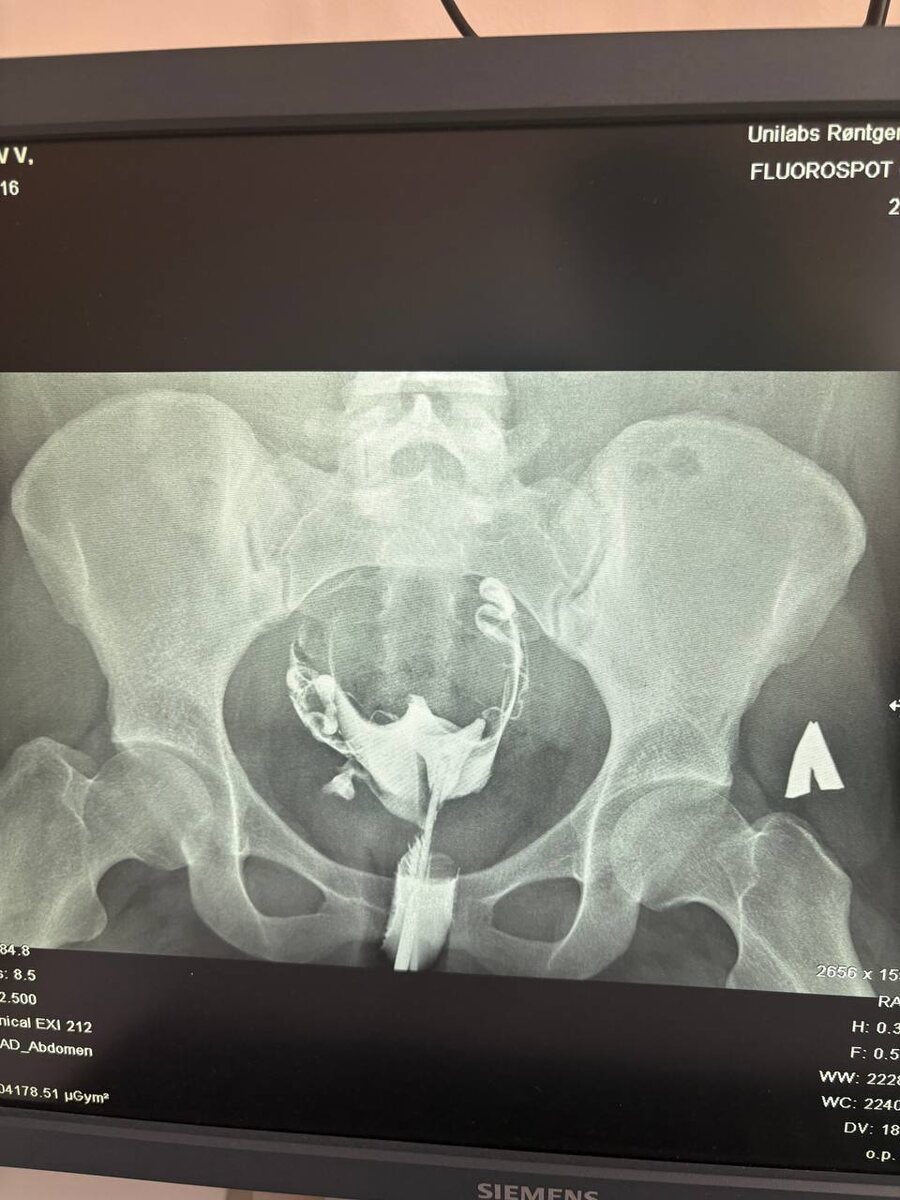

Подготовка к ГСГ (гистеросальпингографии): полный гид от репродуктолога ГСГ — это исследование проходимости маточных труб с помощью рентгена. Назначается, если беременность не наступает больше года. --- 📅 На какой день цикла делать? Идеальное время: 6–12 день цикла (сразу после месячных, но до овуляции). ❌ Нельзя: - Во время месячных - При подозрении на беременность - В середине/конце цикла (риск облучения яйцеклетки) --- 📋 Какие анализы сдать перед ГСГ? 1. Мазок на флору (чтобы исключить воспаление) 2. Общий анализ крови + СОЭ (проверка на скрытые инфекции) 3. Анализы на ИППП (хламидии, уреаплазма, микоплазма — если есть, ГСГ откладывают) 4. УЗИ малого таза (чтобы убедиться, нет кист/острого воспаления) --- 🔍 Как подготовиться за 2–3 дня? ✔ Диета: Легкая пища, избегайте газообразующих продуктов (капуста, бобовые, газировка). ✔ Гигиена: Перед процедурой — душ без спринцеваний. ✔ Обезболивание: За 30–40 минут примите ибупрофен/нурофен (по согласованию с врачом). --- 🚨 Что в

ГСГ — это исследование проходимости маточных труб с помощью рентгена. Назначается, если беременность не наступает больше года.